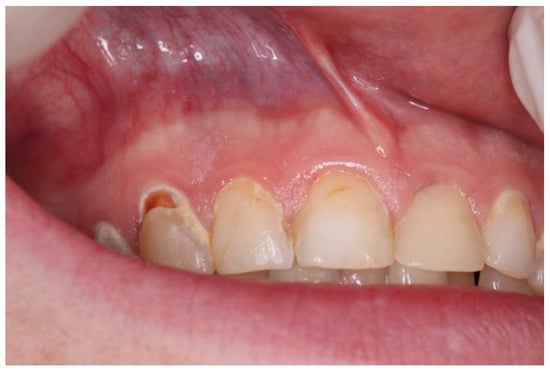

| Snus | 5–10 | 2–5 | White round lesion (Figure 2) | Above tooth nr. 13, 12 |